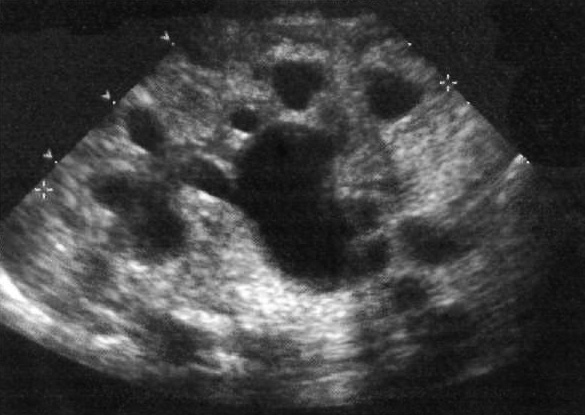

Ультразвуковая картина почек у новорожденных и грудных детей имеет характерные выраженные гипоэхогенные пирамиды мозгового вещества. При гидронефрозе собирающая система почек более гипоэхогенная по отношению к пирамидам, также она соединена между чашечками, тогда как пирамиды не имеют гипоэхогенных соединяющих структур (фото 1). Часто такие отличия трудно определить – в этом случае с целью исключения гидронефроза исследование проводят в положении пациента лежа на животе, применяя высокочастотный датчик (> 8 МГц) (линейный или изогнутый).

Фото 1. Почка новорожденного с умеренным гидронефрозом и задним клапаном уретры. Продольное ультразвуковое изображение: отмечается расширение основной чашечки верхнего полюса и центральной части почечной лоханки